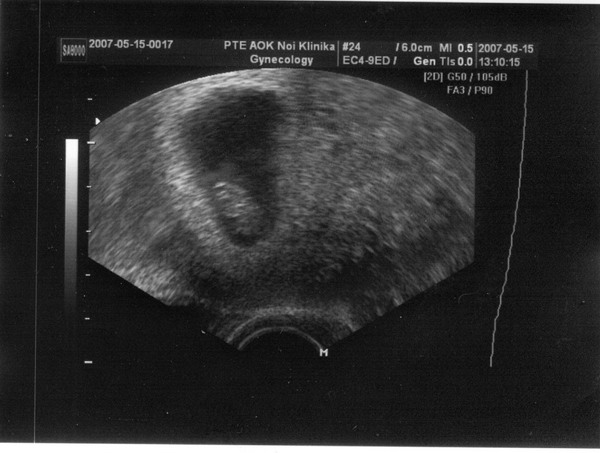

Nagyon jó az UH-s felvétel!! Gratula a szívhanghoz! Szerintem nem kell éhgyomorra menned.

Örülök, hogy UH-n minden OK. Már megint újabb időpont?!?